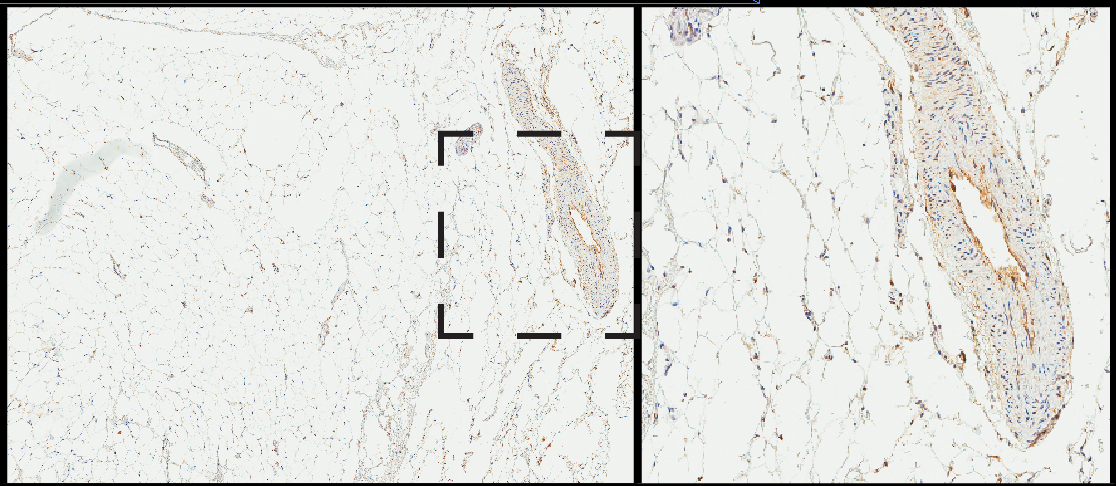

Like most studies, our work on LaNt a31 began with a pilot study. We obtained a small panel of uninvolved (normal) and breast cancer specimens that have been donated to our local research tissue bank. We then used antibodies that we raised and validated against LaNt a31 to localise where and how much of the protein was present in each tissue using a process of “immunohistochemistry” (literally using antibodies (immuno) to probe tissue (histo) and detecting them with a chemical reaction).

In the images below, the brown stain comes from an enzymatic reaction where the antibodies are bound to their target. Broadly speaking, the more brown, the more antibodies are bound and, therefore, the more protein that is present. This type of quantification is not particularly precise in terms of absolute abundance but it does give a reasonable indication of relative abundance. In this small scale study, all the normal tissue specimens gave very little staining in very discrete regions, whereas most of the cancer specimens were strongly stained (examples below). These findings suggested that LaNt a31 might be upregulated in breast cancer and that it would be worth looking at a larger cohort…. so we did!